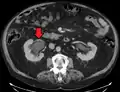

Left sided hydronephrosis in a person with an atrophic right kidney. Stent is also present (image below).

Left sided hydronephrosis, coronal view. Stent is also present.